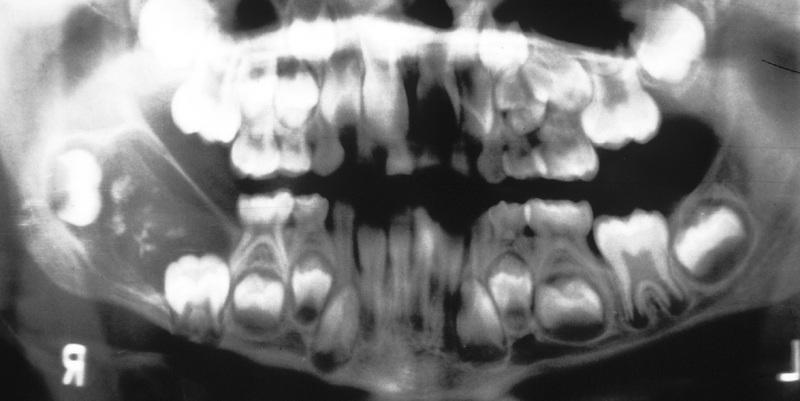

What is the most common type of developmental odontogenic cyst?

dentigerous cyst

Clinical Features

- separation of follicle from crown of an unerupted tooth

- most often involve mandibular third molars (65%)

- most frequent in patients between 10 and 30 years

- slight male predilection, prevalence higher for whites

- asymptomatic (small) or painless bony expansion (large)

- may become infected and cause pain and swelling

- soft tissue analogue of the dentigerous cyst

- soft, translucent swelling in the gingival mucosa

- overlies the crown of an unerupted tooth

- most often seen in children younger than age 10

- most

commonly associated with:

- deciduous mandibular central incisors

- permanent first molars

- deciduous maxillary incisors